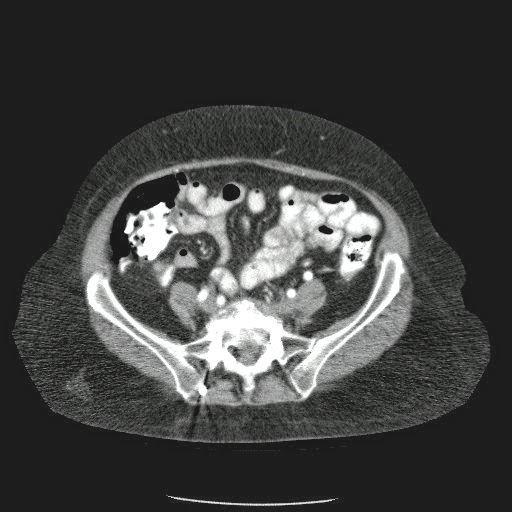

Caso Interesante #4

Adulto masculino, 1 semana de fiebre y malestar general.

¿Dónde esta ubicado el hallazgo?